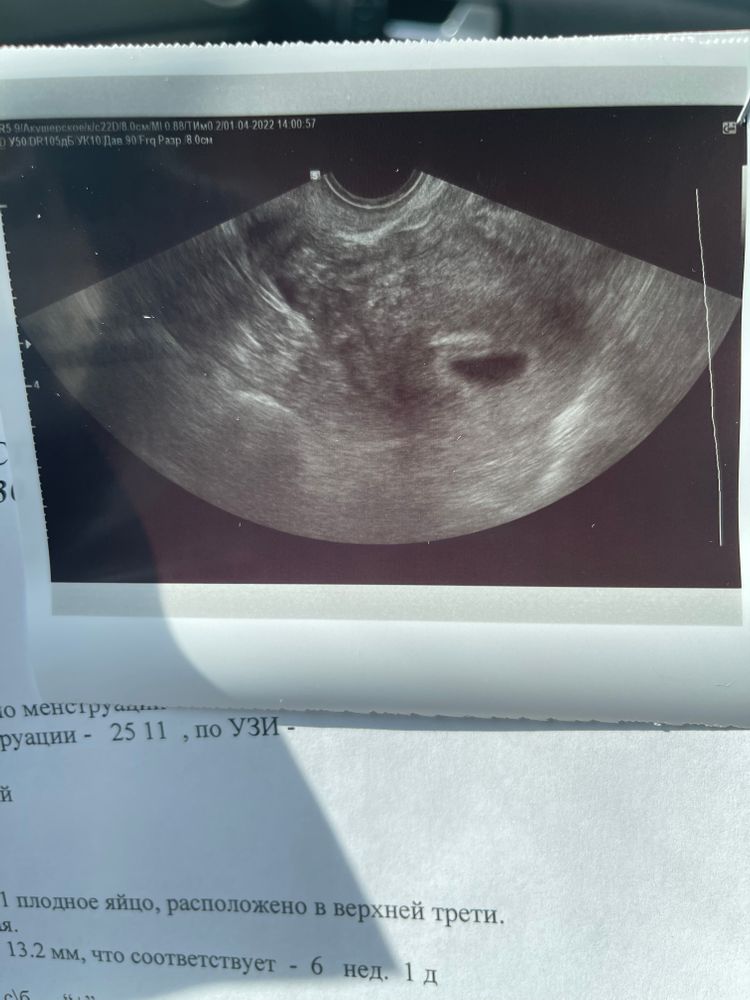

Ровно 6 недель, первое узи

Вчера было ровно 6 недель, сходили на первое узи. Врач сказал все хорошо, малыш развивается согласно сроку, сердечко бьется ❤️В жк пойду вставать на учёт через неделю, записалась на 6 число. Из ощущений : тошнота, головокружение, Грудь болит, тянет на всякую дрянь и хочу спать..Но слава богу нет жуткого токсикоза который был первые 2 беременности, надеюсь уже не начнётся. О моем положении ещё ни кому не говорили, знаем только я и муж, муж в командировке сообщим когда приедет. Муж счастлив как никогда, больше всего хотел ребёночка он , я отнекивалась и говорила давай потом, позже, через годик, потом ещё и так пять лет протянула. Но в этот раз его выстрел был очень метким, я забеременела с 1 раза..Видимо настало время) Как говорить детям не представляю, старшему 14, маленькой 8..Оба говорят что не хотят больше братьев и сестёр, маленькая аж до истерики не надо мне никого..Посоветуйте как можно красиво сообщить всей семье?